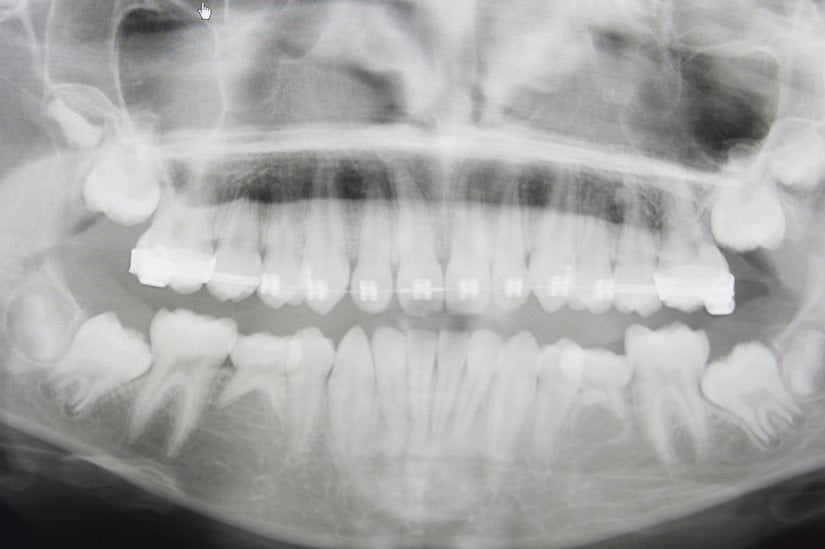

Yirmi yaş dişlerinin sıklıkla gömülü kalırlar, çıktıkları zaman doğru şekilde çıkmazlar ve diğer dişlere sürtünerek onların yapısını bozabilirler. Bu nedenle de ağrı ve enfeksiyona neden oldukları bilinmektedir. Bunun haricinde ise hiçbir işlevleri bulunmamaktadır. Dolayısıyla ağrıya neden oldukları zaman, diş hekimleri tarafından çekilerek hasta rahatlatılabilmektedir. 20 yaş dişleri çekilen kişilerin ağız fonksiyonlarında hiçbir azalma olmamaktadır. Aşağıda bu dişleri görmektesiniz:

Tüm bunlar sonucunda etkilenen organlardan biri de, çene ve diş yapımızdı. Beynimizin büyüyebilmesinin bizlere avantaj sağlamasından ötürü, beyne yer açmak adına ve diyetin de değişmesiyle birlikte çene yapımız küçülmeye başladı. Artık eski güçlü ve vahşi ağızlara ihtiyacımız azalmaya başlamıştı. Otlara göre sindirimi çok daha kolay olan et için fazladan dişlere ihtiyacımız kalmamıştı. İşte bu yüzden de fazladan dişler üretmeye harcanan enerji, başka alanlara harcanabilirdi. Zaten çenenin küçülebilmesi için en dıştan başlayarak dişlerden fedakarlık etmek avantaj sağlamaktaydı.

20 yaş dişleri de popülasyon içerisinde yok olmaya doğru adım adım gitmektedir. Et ile beslenmeye 2.5 milyon yıl önce başladık ve bu sürede, artık işe yaramadığı için ve çenenin küçülebilmesi için yer açmanın avantajlı hale gelmesiyle, insan popülasyonu içerisinde 20 yaş dişleri giderek yok olmaya başladı. Eskiden popülasyonlarda bireylerin %99'undan fazlasında 20 yaş dişlerinin var olduklarını bilmekteyiz, ancak günümüzde, Dünya geneline baktığımızda bazı insanlarda ömürleri boyunca hiç 20 yaş dişinin çıkmadığını görmekteyiz.